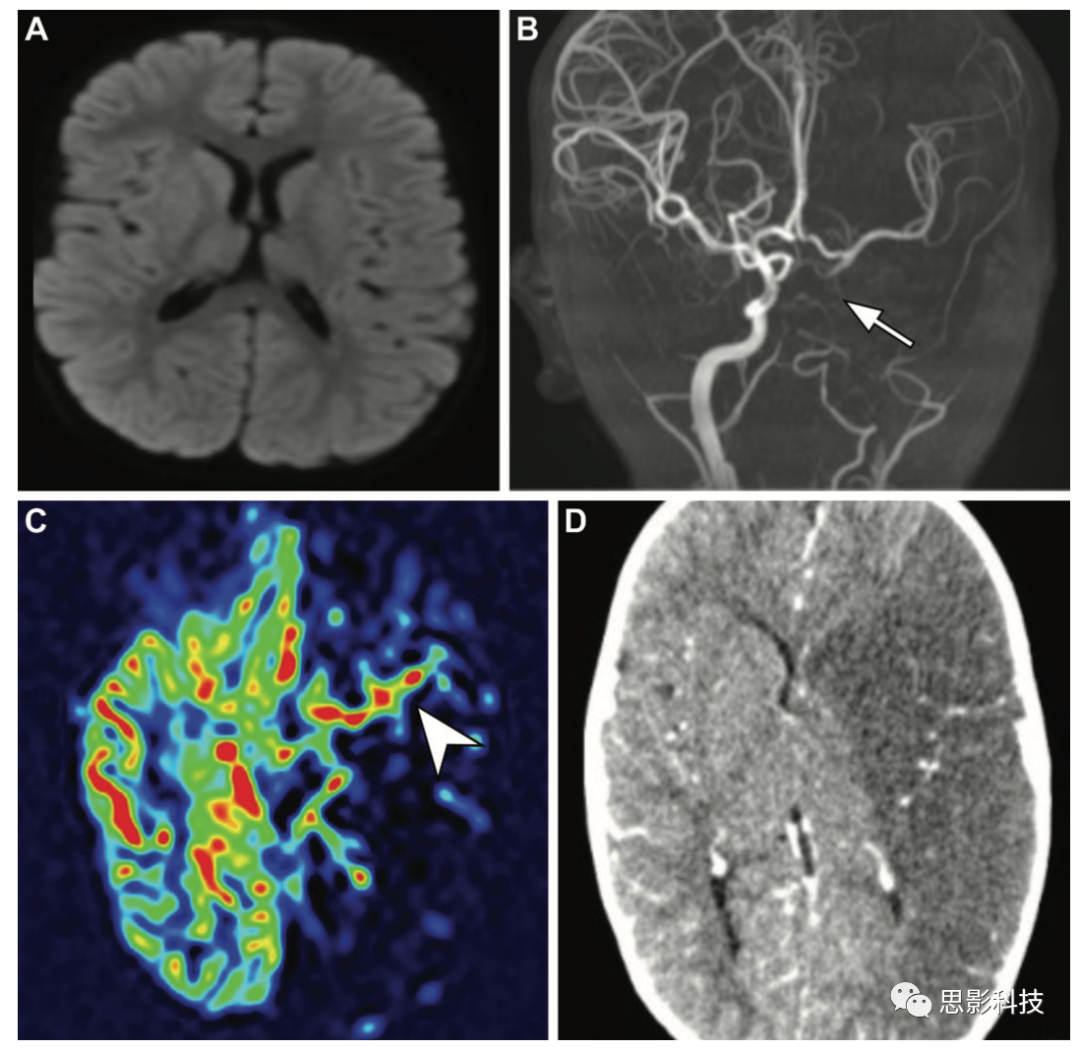

一例5歲兒童心臟手術(shù)后發(fā)生急性缺血性卒中。(A)軸位彌散加權(quán)磁共振成像未顯示患者運(yùn)動(dòng)功能障礙后立即發(fā)生缺血性卒中的證據(jù)。(B)磁共振血管造影顯示左側(cè)頸內(nèi)動(dòng)脈信號(hào)減弱,提示閉塞和左側(cè)頸動(dòng)脈相對(duì)較差的側(cè)支血管(箭頭)。(C)ASL MRI顯示廣泛的低灌注,幾乎整個(gè)左半球的腦血流量減少,表明有危險(xiǎn)的組織和動(dòng)脈傳輸偽影,其表現(xiàn)為左側(cè)sylvian池波形線性高信號(hào)強(qiáng)度,這是由于左側(cè)大腦動(dòng)脈持續(xù)標(biāo)記的自旋(箭頭)

(D)24小時(shí)后獲得的軸位增強(qiáng)CT圖像證實(shí)了廣泛的缺血性卒中,遍及整個(gè)左側(cè)頸動(dòng)脈。